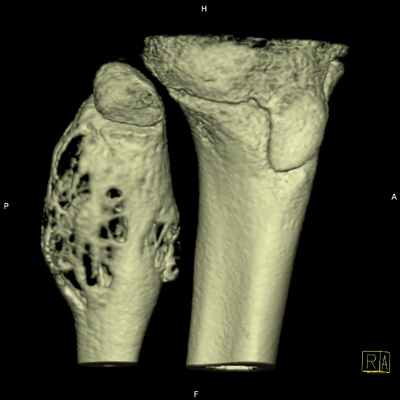

Локализация

Типично локализуюся эксцентрично в метафизах длинных трубчатых костей, прилегая к незакрывшимся зонам роста. Хотя АКК были описаны в большинстве костей, более часто они локализуются в [4,8]

- длинные трубчатые кости: 50-60%, обычно в области метафизов

- нижние конечности: 40%

- большеберцовая и малоберцовая кости: 24%, преимущественно проксимально

- бедренная кость: 13%, преимущественно проксимально

- особенно в задних элементах, в 40% случаев с распространением на тело позвонка [8]